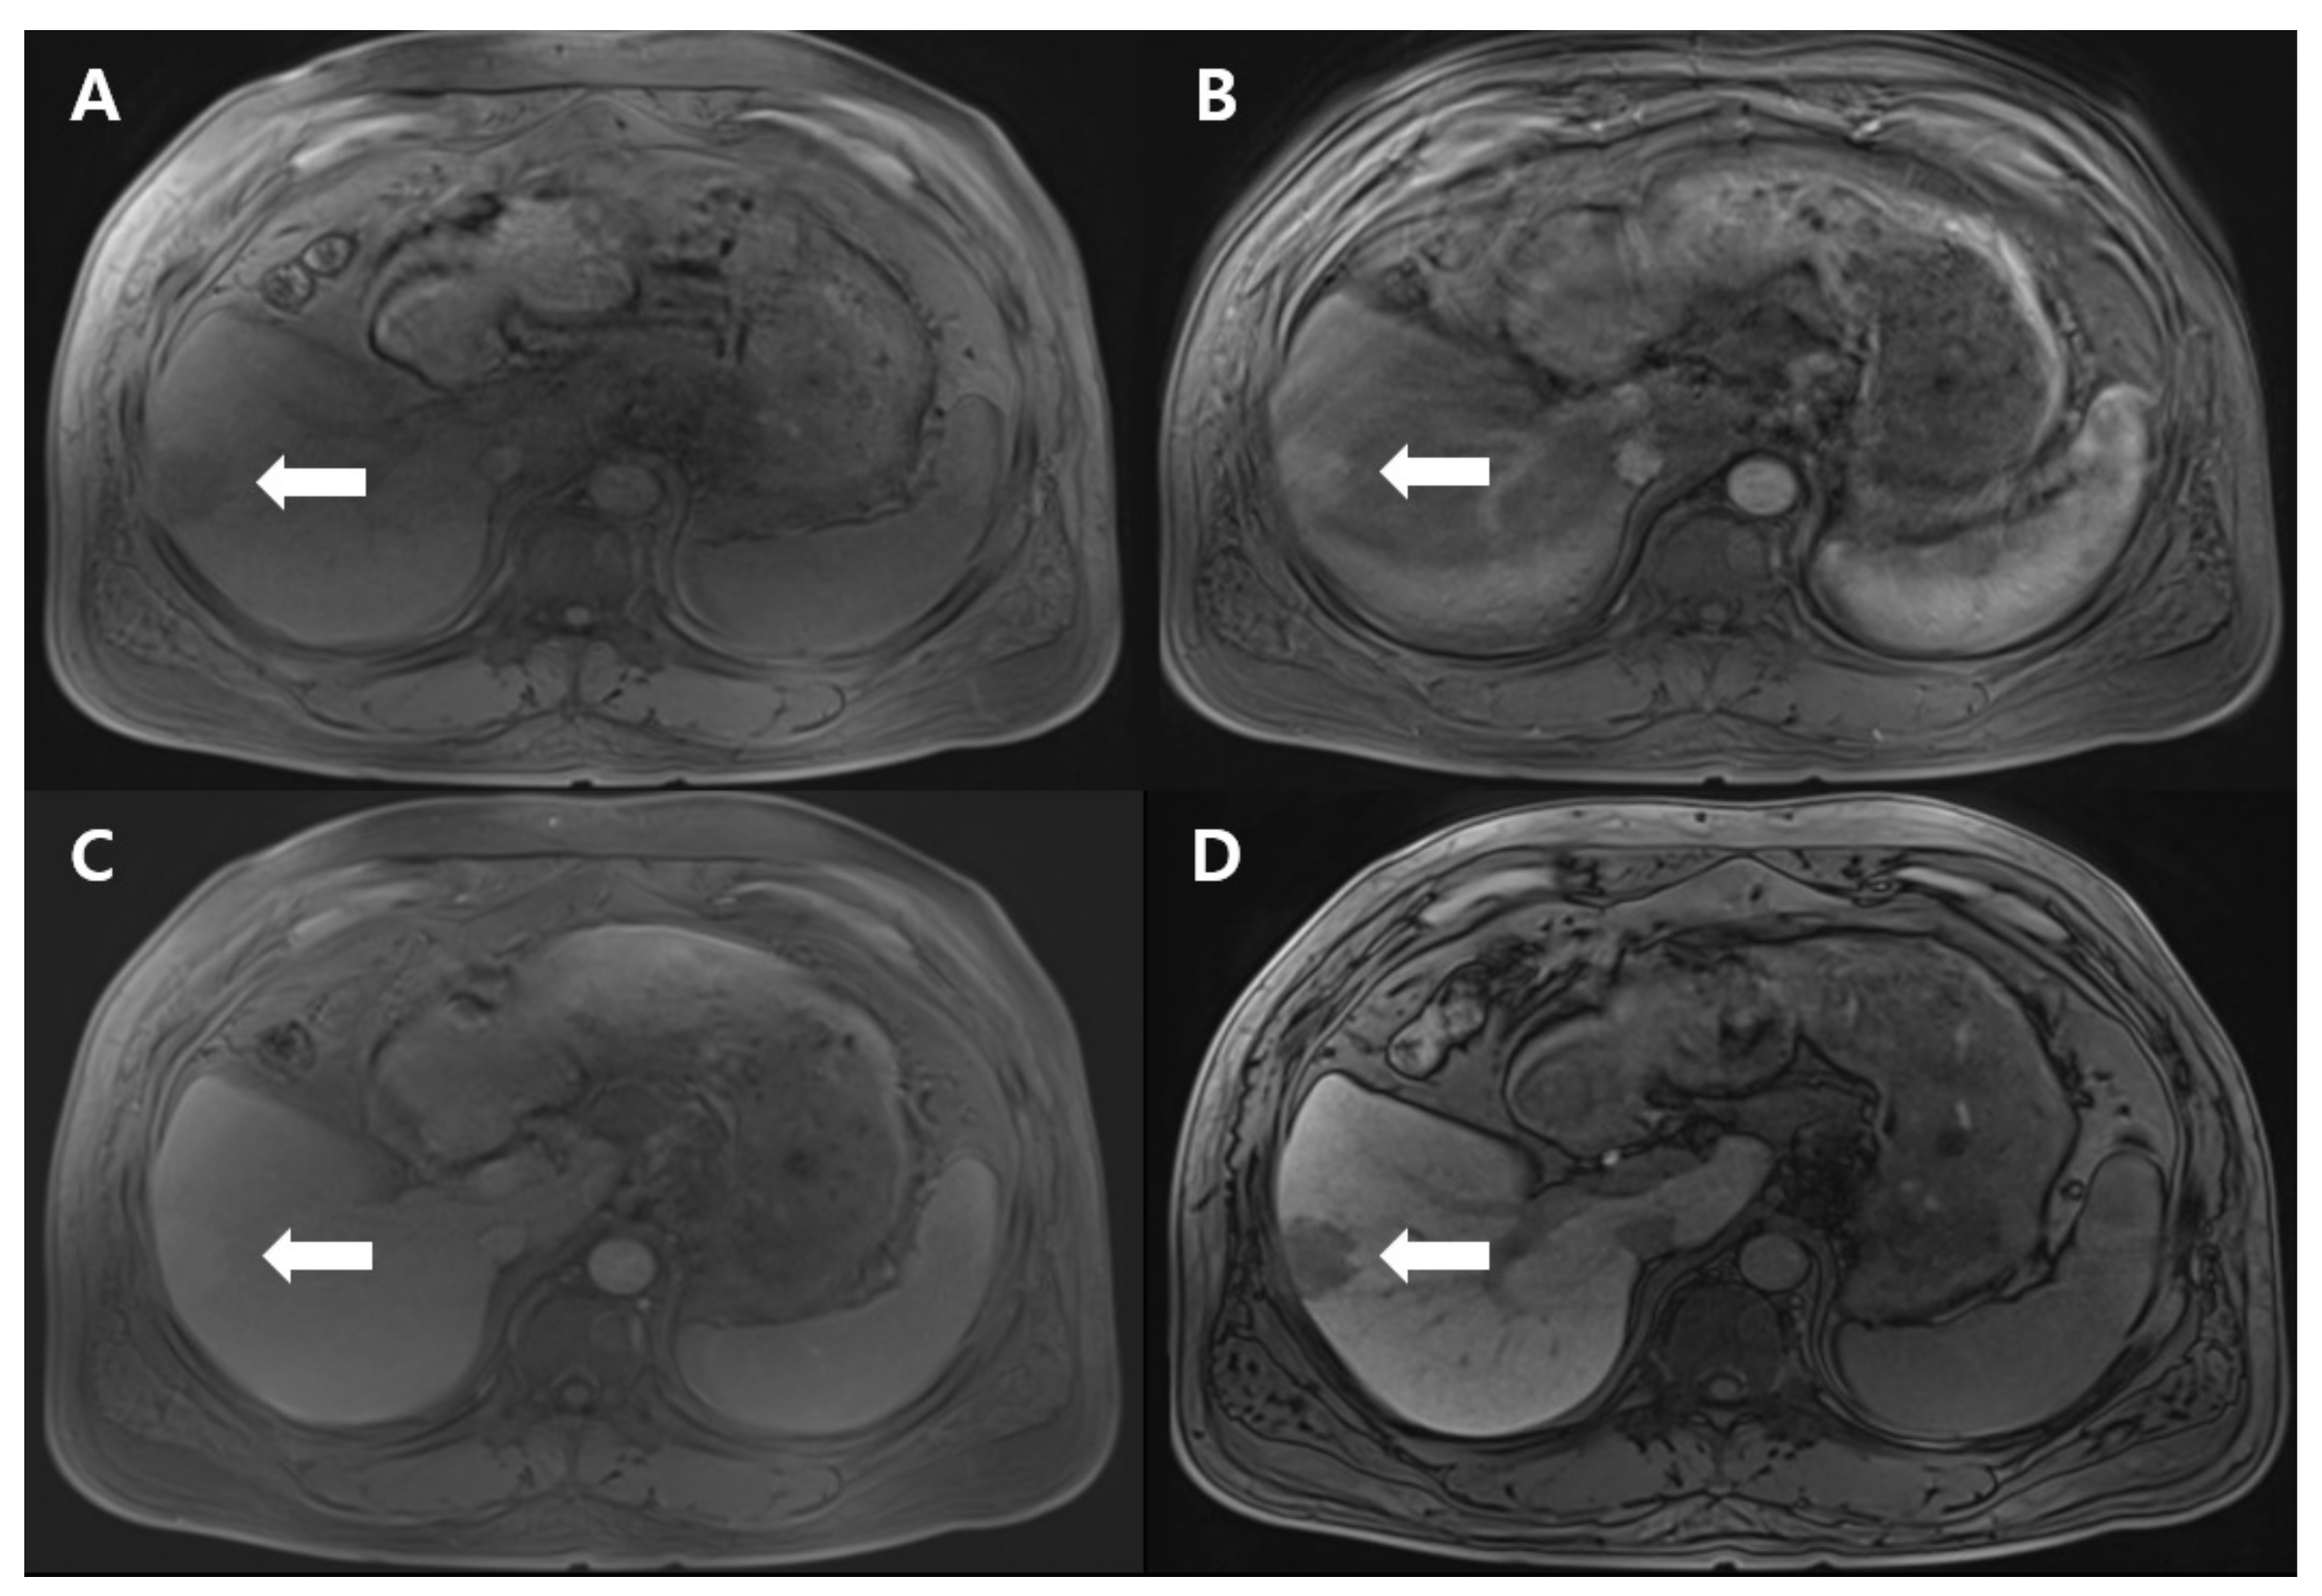

Dynamic T1-weighted MRI revealed a 3-cm-sized, lobulated mass at segment 6, demonstrating hyperintensity in the arterial phase, isointensity in the delayed phase, and hypointensity in the hepatobiliary phase, suggesting the possibility of HCC (Figure 1). Due to the elevated AFP level and the peripheral location of the mass, tumor resection was performed instead of a biopsy.

Figure 1.

T1-weighted magnetic resonance imaging reveals an approximately 3-cm-sized, lobulated, hypointense mass in the pre-contrast phase (A), a hyperintense mass in the arterial phase (B), an isointense mass in the delayed phase (C), and a hypointense mass in the hepatobiliary phase (D), at segment 6. The lesion is indicated by white arrows in all phases.